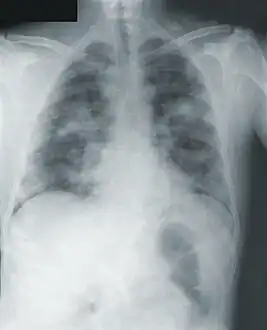

Chest x-ray of pneumonic plague showing bilateral, diffuse interstitial pleural infiltrates, and accompanying consolidation. As well as, what appeared to be marked, mediastinal adenopathy.